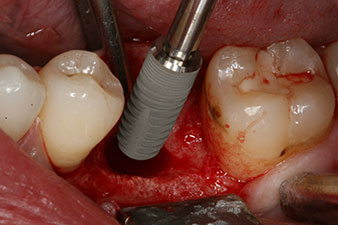

However, six weeks after the extraction incomplete ossification was found after preparation of the mucoperiosteal flap in the region of the former mesial alveolus.

The implant was placed as planned after thorough removal of the granulation tissue (blueSky, bredent).

The torque used for the machine-driven placement was 43 Ncm. In addition, after screwing a measuring post (SmartPeg) specially matched to the implant, the ISQ value was measured with the probe of the W&H Osstell ISQ module.

This module is an optional extra for the W&H Implantmed and is docked to the implantology motor (see Fig. 11). The dimensionless ISQ value immediately after insertion was 64 orovestibular and 68 mesiodistal (maximum value = 100).